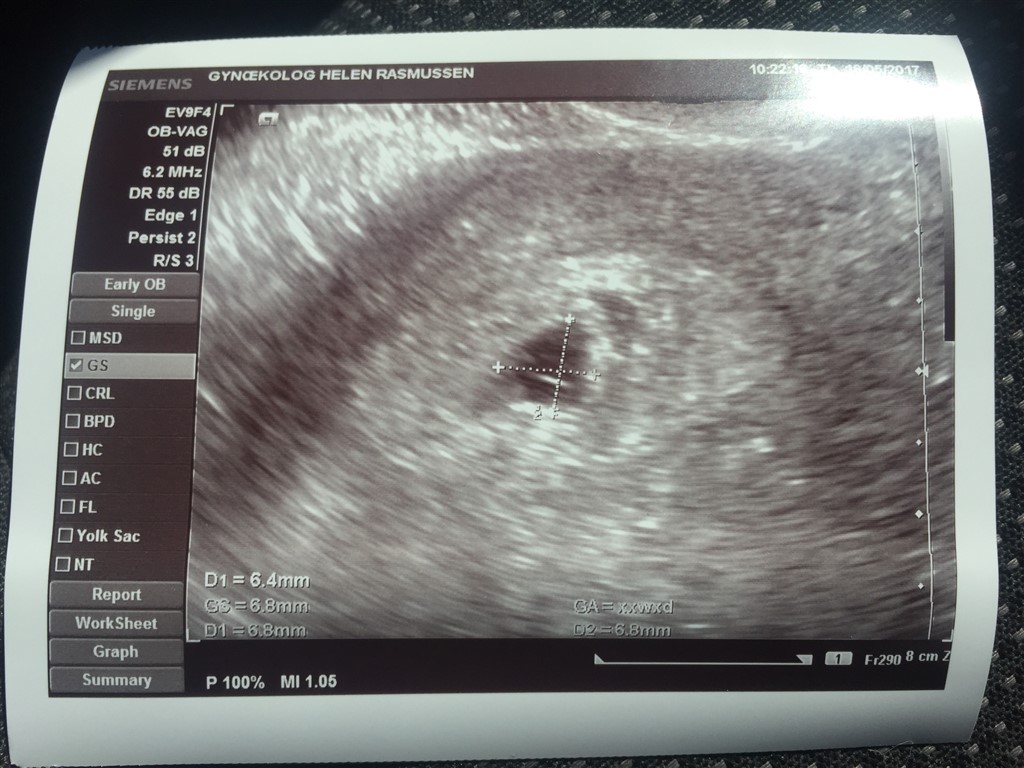

Jeg er SÅ glad! De fandt en fin lille blommesæk på 6,8 mm og måske antydningen af et foster. Hcg var steget til 8500. Det er langt mere, end hvad jeg havde turde håbe på.

MEN - der er en blødning i livmoderen, hvilket forklarer mine pletblødninger (på billedet oppe til højre for blommesækken). Gudskelov er blødningen ikke i den del af livmoderen, hvor graviditeten sidder - men der er øget fare for, at livmoderen reagerer ved at trække sig sammen og udstøder fosteret.